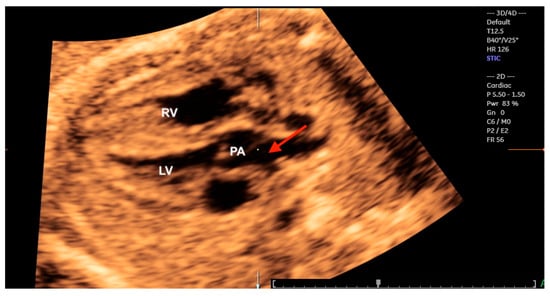

10. Transposition of the Great Arteries

The complete transposition of the great arteries (TGA) is characterized by concordant atrioventricular connection with discordant ventriculoarterial connection, and therefore, does not include the hearts with atrial isomerism. The interventricular septum does not have the usual curvature of the normal heart, reflecting the outflow tracts of the ventricles with the great arteries “in parallel”. In simple TGA, the image of the fetal heart in the 4C view is normal, with altered views of the ventricular outflow tracts due to ventriculo-arterial concordance and ventriculoarterial discordance with the great arteries in a parallel relationship. Double outlet right ventricular outflow tract with the anterior aorta, known as a Taussig–Bing anomaly, remains a challenging differential diagnosis for TGA. The presence of a subpulmonary ventricular septal defect with both great arteries originating predominantly (>50%) from the morphologically right ventricle and subpulmonary stenosis may be helpful in the diagnosis of a Taussig–Bing anomaly [54]. Therefore, its prenatal detection rate remains low. In these cases, advanced technologies can be important diagnostic tools by providing anatomical details of the ventricular outflow tracts (Figure 22, Figure 23 and Figure 24) [34,55,56]. It is important to note that 3D images can sometimes be more difficult to obtain and interpret than standard 2D images for an examiner who is not experienced in advanced ultrasound technologies and who is not an expert in cardiac anatomy.

Figure 22.

Transposition of the great arteries. Reconstruction of the left ventricular outflow tract using Spatiotemporal Image Correlation in the rendering mode from a 4-chamber view of the fetal heart. Note the bifurcation of the pulmonary artery (red arrow); LV: left ventricle; PA: pulmonary artery; RV: right ventricle.